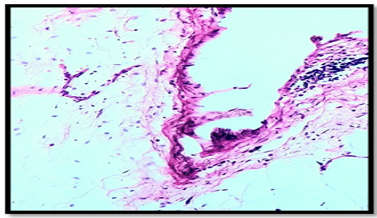

A 52-year-old woman with a history of diabetes mellitus, hypertension, heart failure functional class I, primary hypothyroidism, Cushing’s syndrome of pituitary origin, treated with bilateral adrenalectomy. During the follow-up of Cushing’s syndrome, presents intermittent painful, without dyspnea or weight loss. Computed tomography (CT), shows an oval image, lobulated contours, well delimited, homogeneous, with a density of 20 UH, which extends from the prevascular space to the upper and lower paratracheal of 4.1 x 3.2 x 5.7 cm. (Figure 1a, b, c ). After evaluation by the surgeon, surgery is decided. Performed posterolateral thoracotomy+ mediastinal tumor resection, we found in medium mediastinum a tumor of 7 cm, lobulated, cystic aspect related in the anterior side with superior vena cava, external side vein with azigos vein, and internal side with aorta. Report histopathology is cavernous lymphangioma (Figure 2a, b, c ).

Histologically, lymphangiomas are thin-walled unilocular or multilocular cystic tumors lined by endothelial cells that contain a light-yellow fluid [6]. They are subdivided into three types according to the size of the lymphatic channels they contain, cystic, capillary and cavernous. Cystic lymphangiomas are the most common, and the cavernous type is relatively rare [2]. Cavernous lymphangiomas present indiscrete margins and insinuate themselves into the surrounding structures [5]. Immunohistochemistry staining for CD31 confirms the diagnosis of mediastinal cystic tumors, as well as positive D2-40 staining for the endothelium of the lymphatic vessels and positive staining of the epithelium with cytokeratin AE1/3. The cavernous lymphangiomas have discrete amounts of loose connective tissue compared with the cystic lesions, which may be covered with thick adventitia. The connective tissue stromas consist of varying amounts of smooth muscle cells in the form of a spindle, bundles of collagen, fibroblasts and lymphocytes. The presence of benign lymphoid aggregates is useful in the identification of lymphangiomas. The cellular components are generally well differentiated and lack cytological atypia [5].